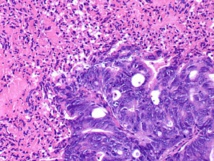

El medio en que se desarrollan los tumores es, en comparación, mucho más ácido que el medio de un tejido normal, pues las células tumorales “consumen más glucosa y segregan ácidos como producto de desecho”, afirma el doctor Mark Robsertson-Tessi, investigador del Departamento de Oncología Matemática Integrada de Moffitt.

Partiendo de esta base, las diferencias que se pueden observar dentro del propio tumor son similares. El metabolismo de la glucosa es mayor en la zona central del tumor, y la producción de ácidos se reduce en las zonas exteriores. La consecuencia de esto es que las células centrales sean mucho más agresivas y tiendan a expandirse hacia fuera, dando así lugar al comportamiento invasivo del tumor.